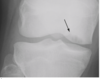

26 M with traumatic knee injury Dx?

Segond Fracture Avulsion fracture of lateral tibial plateau Attachment site of LCL Sport injurie flexed knee + internal rotation + varus stress Oval shaped fragment adjacent to lat. Tibia plateau